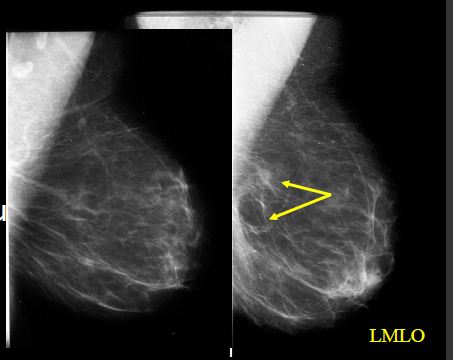

Ca prsu

Kazuistika 1

- Klientka vyšetřena v 2006, MMG+UZ – bez ložiskových změn

- MDL dx – technicky nesprávná

- Následně vyšetřena 2009 s nálezem léze v HQ dx preaxilárně

Kazuistika 2

- Klientka s nálezem nepravidelného zastínění při bazi sin

- Na kontrolním snímku správně zhotoveném není patrná

- Dobré vytažení!!! Komprese!!!

Kazuistika 3

Klientka odeslána do FN HK s Hi (CCB) ověřenými mikrokalcifikacemi

na rozhr.ZQ sin

- pouze v MDL projekci zachyceno 4mm ložisko v HQ

- popsáno jako intramam.LU, nemá korelát v KK

- Ve FN HK před výkonem zhotoveny KK a MDL projekce sin

- Ložisko v KK projekci (CCB Hi.duktální Ca)